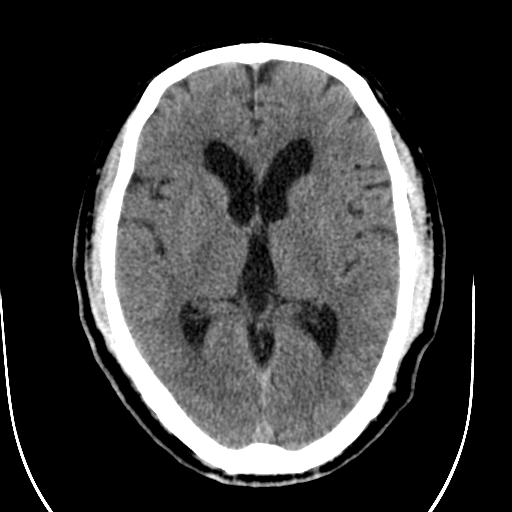

标题: CT28335:男,58岁,请各位看看是不是有脑积水,蝶窦内高密 [打印本页]

标题: CT28335:男,58岁,请各位看看是不是有脑积水,蝶窦内高密

轻度积水,蝶窦正常。

脑积水!建议行mri!

1)脑积水。2)副鼻窦炎。